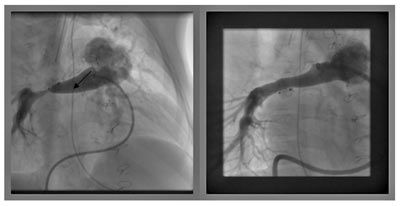

Οι φωτογραφίες δείχνουν τη σύγκλειση βοταλλείου πόρου με συσκευή τύπου ομπρέλας

Η διαδερμική σύγκλειση του βοταλλείου πόρου αποτελεί ασφαλή εναλλακτική μέθοδο της χειρουργικής και συνιστά τη μέθοδο εκλογής στις περισσότερες περιπτώσεις.